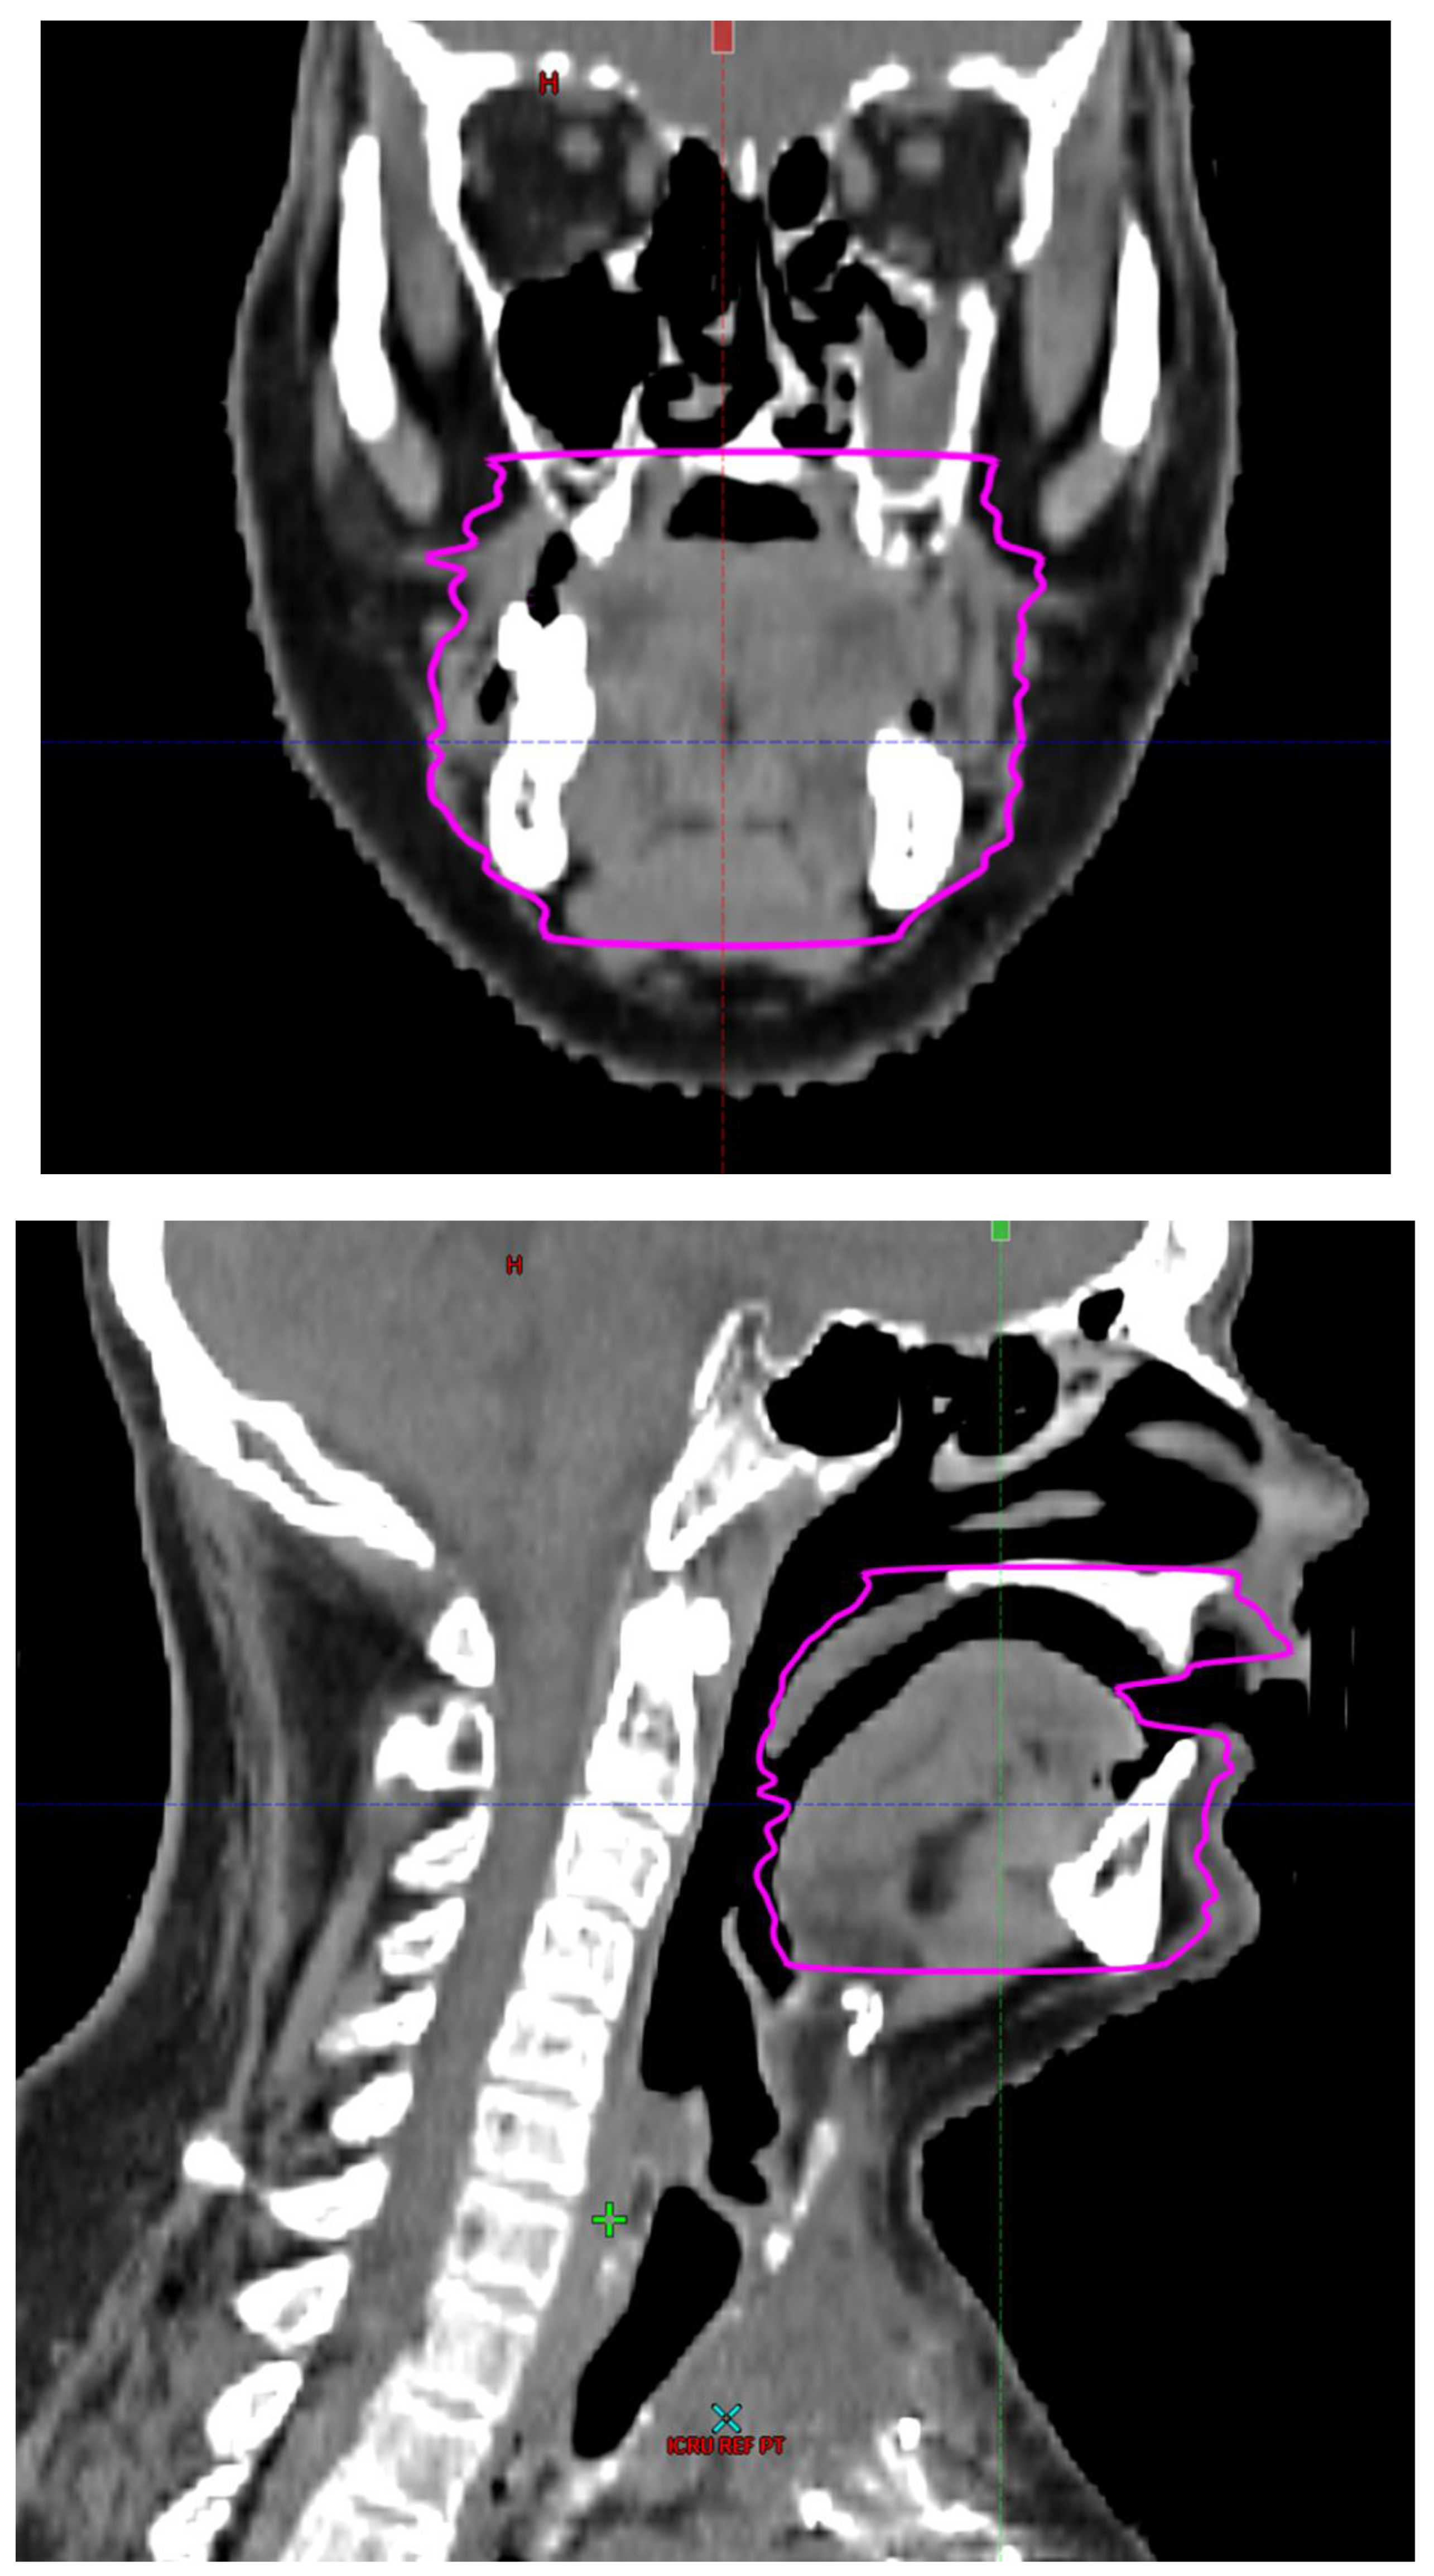

Radiotherapy treatment plans were created, and dose volume histograms (DVH) were generated using the Eclipse treatment planning system (Varian Medical Systems, Palo Alto, CA). The standard photon treatment plans consisted of three volumetric modulated arc therapy fields. The standard proton treatment plans consisted of three to four fields with the pencil beam scanning technique. For proton therapy plans, the RT dose was scaled by 1.1 to account for the difference in relative biological effect when compared to conventional photon treatments. A definition for oral cavity OAR avoidance structure evolved at our institution between 2003 and 2016 when it was formalized and accepted as the consensus standard for treatment planning (Figure 2). The DVH statistics for the oral cavity OAR, and the mean dose to the left and right submandibular glands, left and right parotid glands and total parotid glands were calculated and extracted. Pharyngeal constrictor, intrinsic and extrinsic muscles of the tongue, and laryngeal DVH statistics were not included since swallowing function is not a primary endpoint for this study. There were four patients who did not complete the planned course of treatment. In these cases, the prescribed dose was scaled to the delivered dose.

The superior extent of the oral cavity OAR avoidance structure includes all the mucosa of the hard palate. The contouring of the OAR begins superiorly at the first sign of mucosa on the alveolar ridge of the maxilla (medial and lateral) and hard palate. It then continues inferiorly to include the mucosa of the upper and lower lip, mucosa of the hard and soft palate including the uvula, the buccal mucosa including the buccinator muscles, the mucosa of the retromolar trigone, the entire tongue (anterior two-thirds, dorsal surface and tongue base), floor of mouth, sublingual glands, gingival mucosa of the mandible (lingual and buccal surfaces), and ending at the level of the cranial edge of the hyoid bone and caudal edge of the mandible. It also includes the maxillary and mandibular teeth if present. The posterior extent includes the soft palate, uvula, and tongue base. The anterior extent includes the mucosal surface of the posterior one-half of the lips and the gingival mucosa of the maxillary and mandibular alveolar ridges and retromolar trigone. The lateral extent includes the buccal mucosa and buccinator muscles. The oral cavity OAR contains most of the taste buds which are located within the mucosa of the anterior two-thirds of the tongue, the floor of mouth, the buccal mucosa, the lips, the pharynx (including the soft palate, uvula, and base of tongue), the larynx (epiglottis) and upper third of the esophagus [4]. The oral cavity OAR also contains the minor salivary glands located within buccal, labial, lingual, soft palate, lateral parts of the hard palate, and floor of the mouth submucosa and in the trough circling the circumvallate papillae on the dorsal surface of the tongue near the terminal sulcus [3]. Therefore, the oral cavity OAR for radiotherapy (RT) treatment planning purposes is defined as including the anterior two-thirds of the tongue, floor of mouth, buccal mucosa, mucosal surface of the lips, soft palate, uvula, base of tongue, hard palate and circumvallate papillae on the dorsal surface of the tongue. The gingival mucosa of the alveolar ridges of the mandible and maxilla and the mucosa of the retromolar trigone are also included in the definition to further reduce the incidence and severity of painful oral mucositis. Finally, the sublingual glands are included in the oral cavity OAR structure. The larynx (epiglottis) and upper third of the esophagus are not included in this OAR volume because they are included in their own OAR avoidance structure (larynx, cricopharyngeal inlet, cervical esophagus).

Figure 2. Oral Cavity Organ at Risk (OAR) Avoidance Structure Definition.

Preprints 93045 g002aPreprints 93045 g002bPreprints 93045 g002cPreprints 93045 g002d